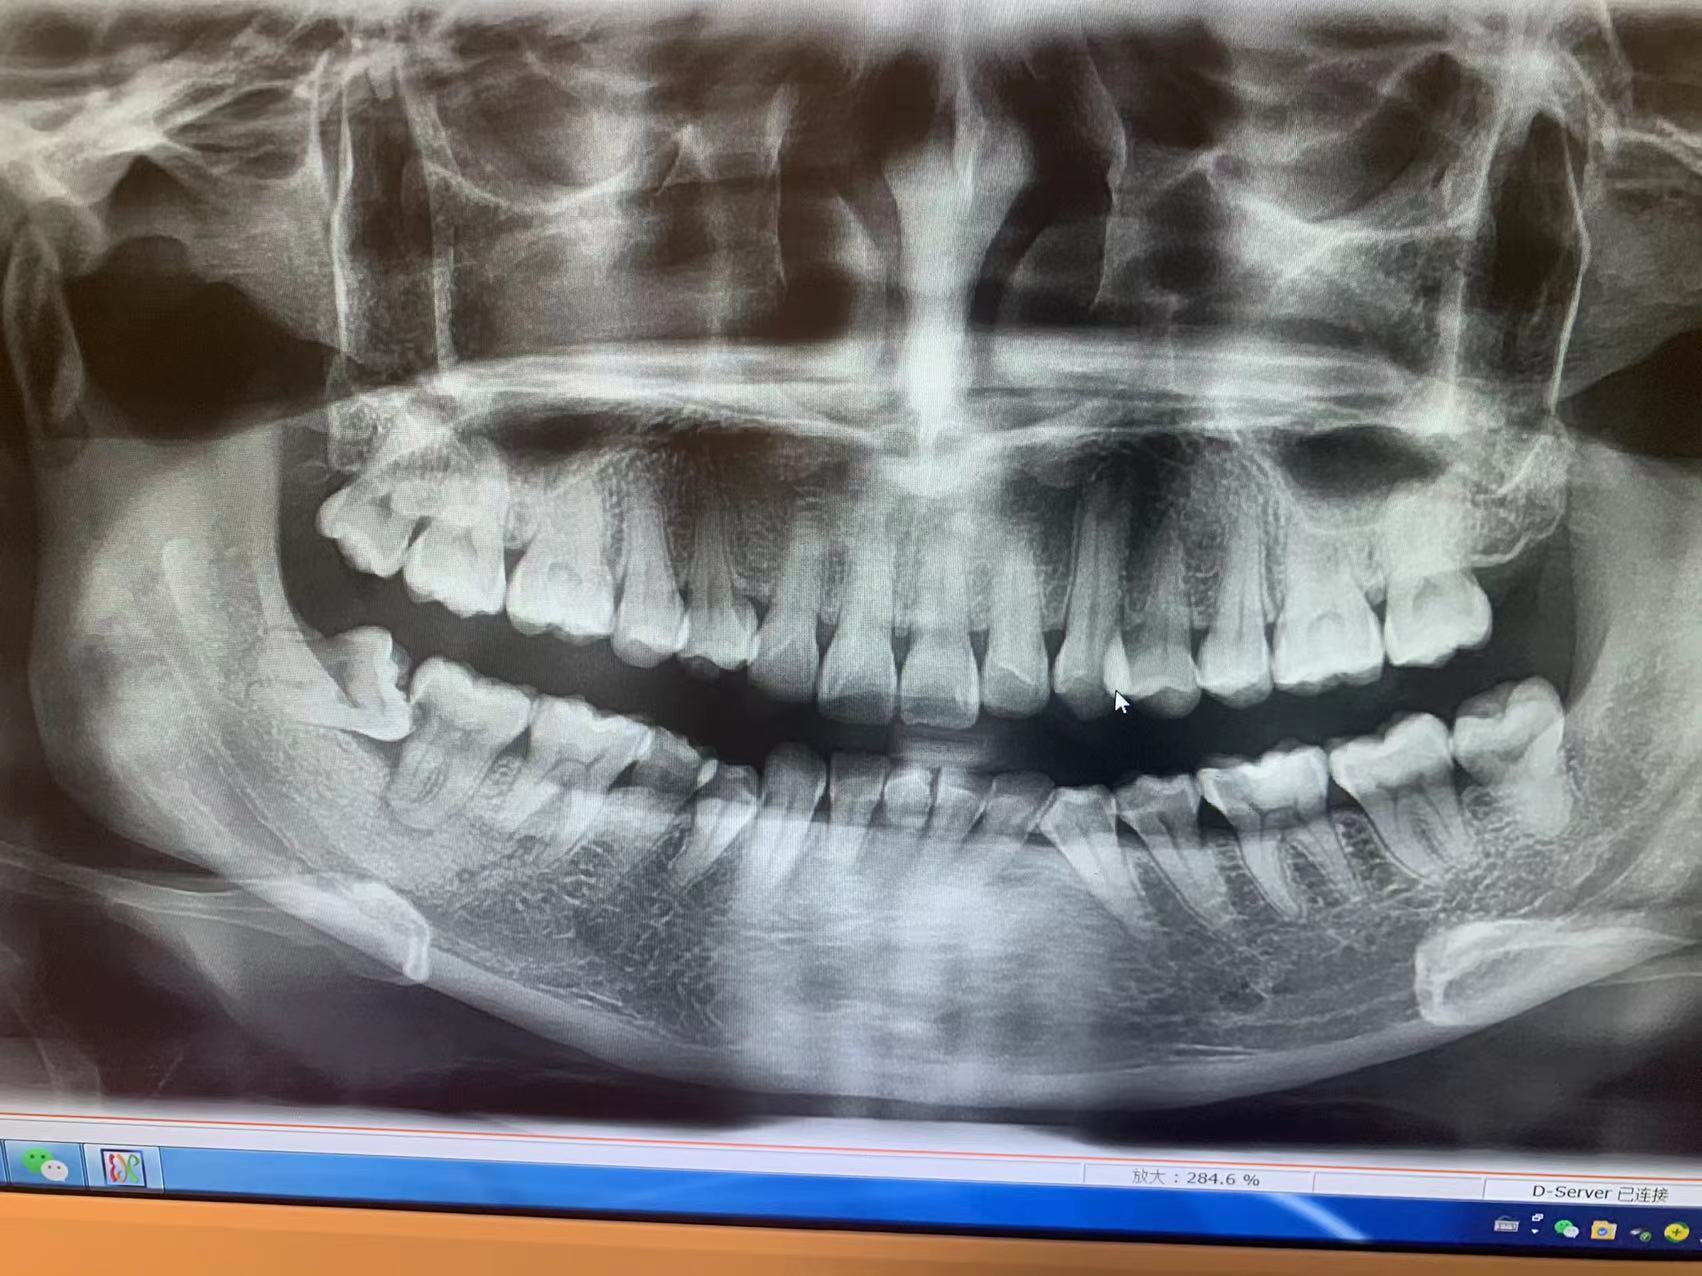

郑州精益口腔医院有限公司以数字化设备为辅助,促进诊疗能力的升级。

我们与国内外医疗器械品牌保持长期合作关系,引进了口腔CBCT全景机、根管显微镜、

口腔激光治疗仪、数字化口腔扫描仪等机械设备。